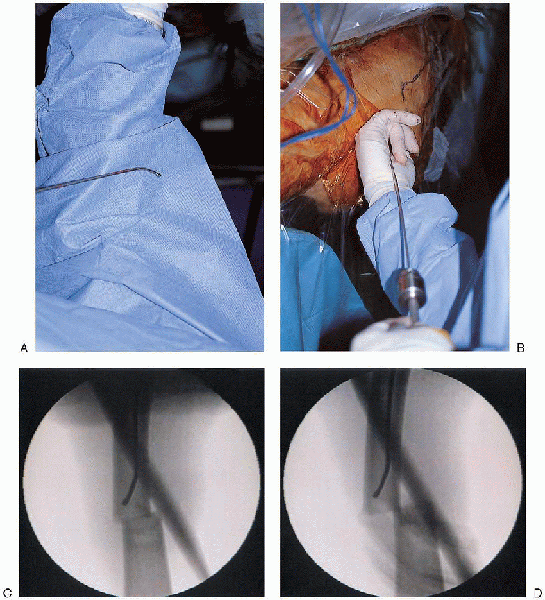

FIGURE 36-15. Use of a 3.2-mm tip-threaded guide pin from the sliding hip screw set to open the medullary canal (A); after its position is verified on the anteroposterior and lateral views (B and C), the entry portal is enlarged with a cannulated reamer (D and E). (continued)

|

creation of the entry portal, a ball-tipped guide rod attached to a

T-handled chuck is placed down the femoral canal to the fracture (Fig. 36-16).